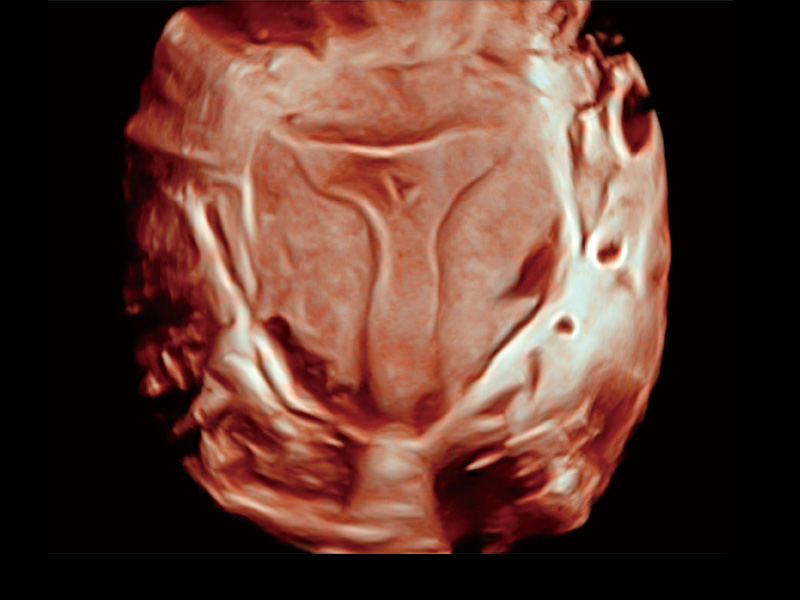

腔内容积探头

腔内三维成像技术获得显著提升,超大扇角在满足日常基础扫查的同时,支持卵泡自动测量及多种三维渲染模式,为您提供更多的诊断信息,尤其是在子宫畸形的诊断,内膜及肿瘤占位观测中起到了重要的作用。

单角子宫

子宫内膜息肉